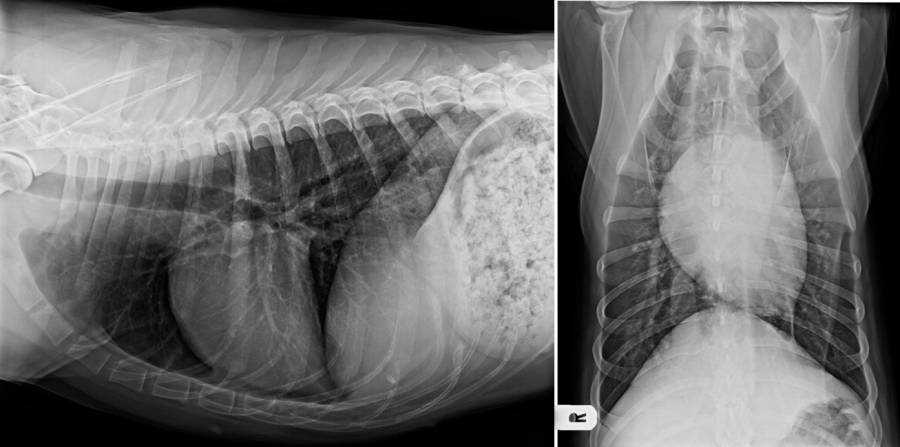

- Lagerung Thorax und Abdomen

- Standard rechtsanliegend

- grundsätzlich immer Grundbilderpaar: 2 Ebenen

Röntgen Thorax

Röntgen Abdomen